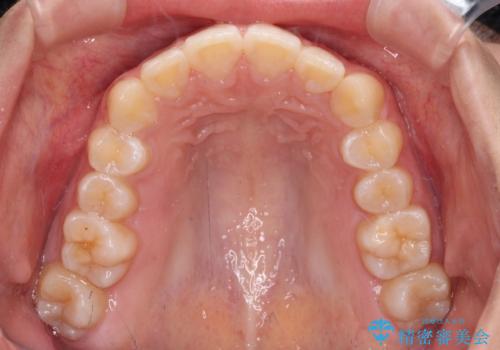

- 前歯の叢生を気にして来院された患者様です。

奥歯の咬み合わせを見ると、上顎が下顎に対して相対的に前方にあり、上下の前歯が接触していない状態でした。

咬み合わせを改善するためには、上顎臼歯を後方に移動させた咬み合わせにする必要があります。

インビザライン単体で改善することも可能ですが、咬合力が強く、単位で達成する可能性が低いと考えられたため、カリエール・ディスタライザーという補助装置を併用して、より確実性を上げることとしました。

奥歯の咬み合わせを改善しながら、並行してインビザラインで歯列を整えることとしました。